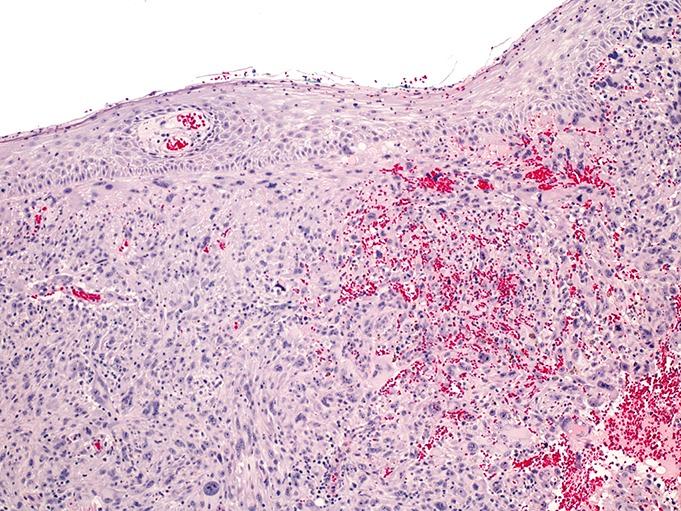

Speiser Jodi J, Aggarwal Smitha, Wold Lindsay, Tung Rebecca, Hutchens Kelli A

Departments of *Pathology, and †Dermatology, Loyola University Medical Center, Maywood, IL.

Am J Dermatopathol. 2015 Dec;37(12):950-3. doi: 10.1097/DAD.0000000000000208.